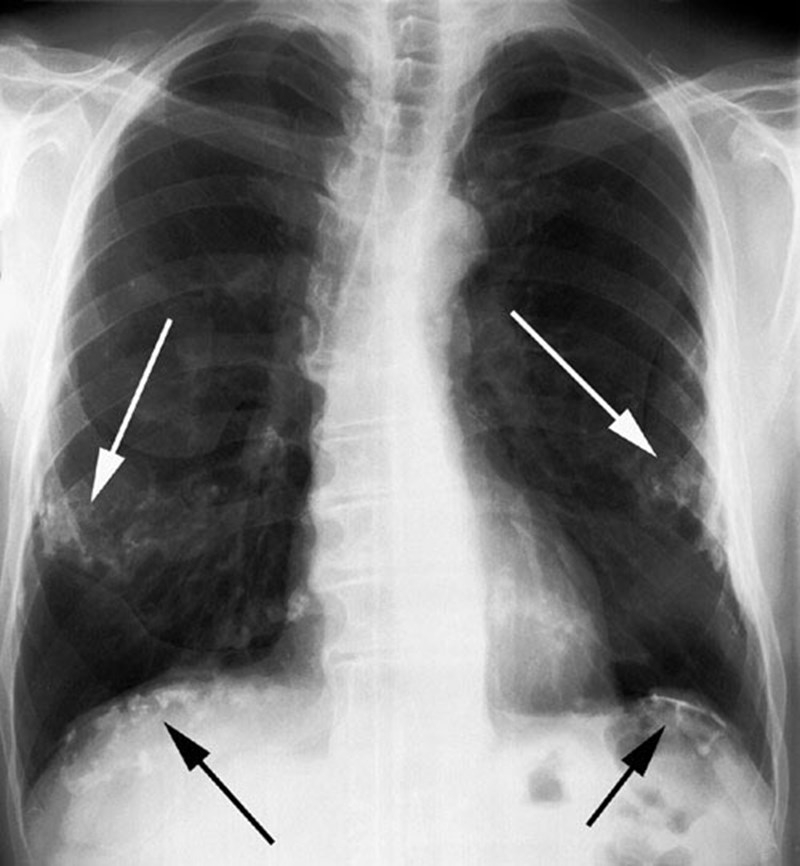

Xơ phổi: Triệu chứng, nguyên nhân và phương pháp điều trị bệnh 1 Xơ phổi là tình trạng các mô trong phổi bị tổn thương

Xơ phổi hay xơ hóa phổi là tình trạng các mô trong phổi bị tổn thương, dày lên và xơ cứng vì tính đàn hồi đã mất và gây sẹo ở phổi. Chính những vết sẹo ở phổi đã ngăn chặn và cản trở hoạt động hít thở của người bệnh, từ đó làm người bệnh khó thở. Bên cạnh đó, xơ phổi cũng gây ra những biến chứng nguy hiểm khác.

Xơ phổi: Triệu chứng, nguyên nhân và phương pháp điều trị bệnh 1 Bệnh xơ phổi có các triệu chứng gì?

Triệu chứng, biểu hiện xơ phổi